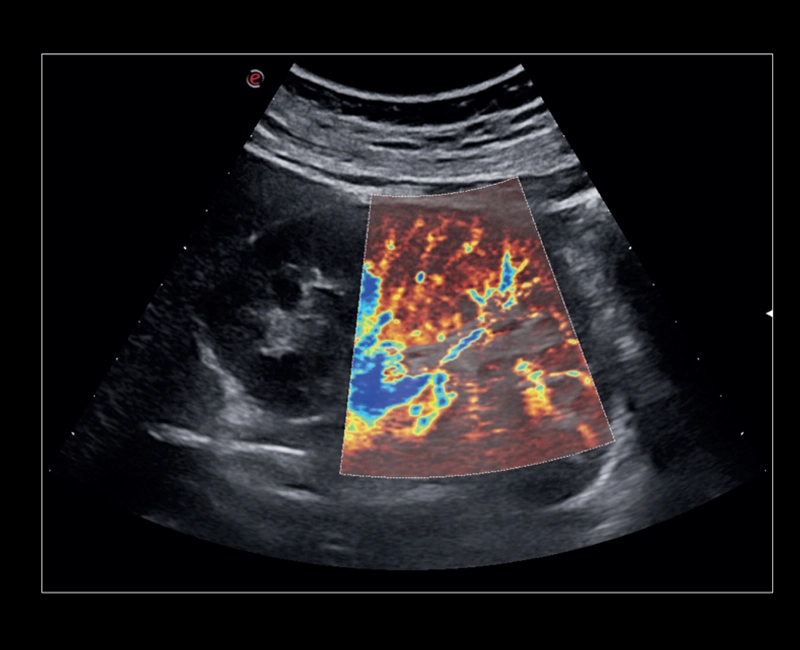

MyLab™9 Platform - XFlow Doppler enhancement in liver vascularization

MyLab™9 Platform - XFlow Doppler enhancement in liver vascularization

MyLab™9 Platform - Hemodynamics analysis using microV on kidney

MyLab™9 Platform - Hemodynamics analysis using microV on kidney